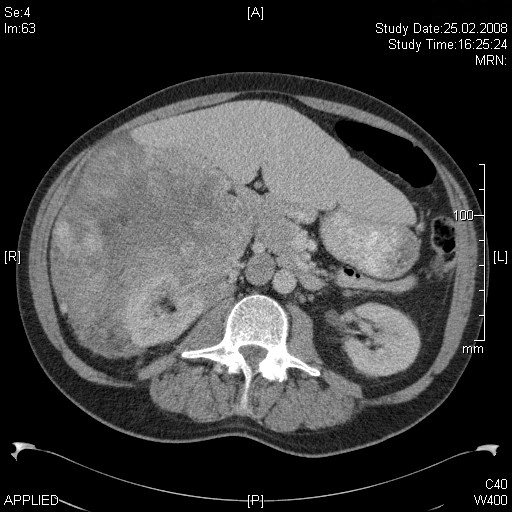

Weichteilsarkome sind bösartige Geschwulste, welche nicht wie Karzinome (Krebs) von Häuten oder Schleimhäuten ausgehen, sondern von den dazwischen liegenden Weichteilen, wie z.B. Muskeln, Bindegewebe oder Fettgewebe. Am häufigsten sind sie in den Extremitäten z.B. Oberschenkel (MRI eines Liposarkoms am Oberschenkel) oder im Fettgewebe hinter den Därmen (Retroperitoneum) lokalisiert (CT eines retroperitonealen Liposarkoms). Diese Geschwulste sind selten und bedürfen einer speziellen Behandlung, deren Hauptbestandteil die radikale, chirurgische Entfernung der Geschwulst ist. Die Behandlung ist interdisziplinär, wird also von verschiedenen Spezialistinnen und Spezialisten in Absprache durchgeführt und sollte an einem damit erfahrenen Spital erfolgen. In der Spital Thurgau haben wir in den letzten 10 Jahren durch ein hohes Aufkommen solcher Tumoren viel Erfahrung mit der Behandlung gewonnen (Statistik Weichteilsarkome am Kantonsspital Münsterlingen). Patientinnen und Patienten mit diesem Leiden werden durch unser Tumorboard beurteilt, die Behandlung festgelegt und anschliessend durchgeführt. Das Vorgehen wird eng mit dem Sarkomboard des Universitätsspitals Zürich abgestimmt und entspricht den Leitlinien des Swiss Sarcoma Advisory Boardes.

Die Operation ist der zentrale Teil einer kurativen (heilenden) Behandlung des Tumors. Bei der Operation wird der Tumor samt einem Mantel von gesundem Gewebe aus der Umgebung herausgelöst (Tumorausräumung retroperitoneal. Zustand nach der Tumorentfernung: der Patient ist 8 Jahre nach der OP tumorfrei und gesund). Alle Organe und Muskeln und Körperteile, welche mit dem Tumor in Berührung kommen, müssen ganz oder teilweise mitentfernt werden. Da dies zum Teil sehr grosse Tumoren sind und dadurch die Operationen auch sehr ausgedehnt sein können, erfordert diese Chirurgie eine grosse Erfahrung in diesem Gebiet (Wide-Excision am Oberschenkel. Die Patientin ist 6 Jahre nach der OP tumorfrei und gesund).